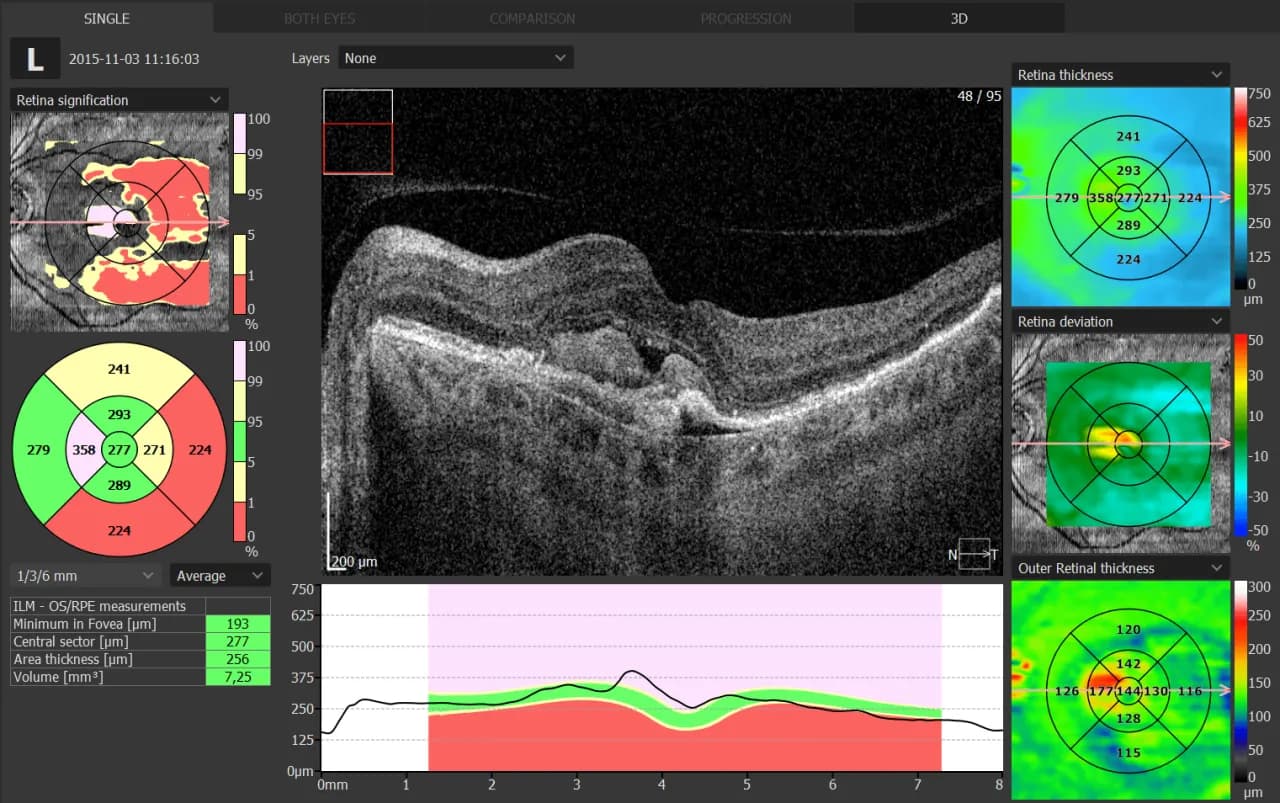

OCT pozwala również na wykrycie i monitorowanie wysiękowej postaci AMD. Zastosowanie OCT umożliwia obserwację gromadzenia się płynu pod siatkówką lub w jej obrębie, co jest kluczowe dla wczesnego rozpoczęcia leczenia. Ponadto, badanie to pomaga w ocenie skuteczności terapii, umożliwiając precyzyjne śledzenie zmian w grubości siatkówki i ilości płynu w czasie. Dzięki temu OCT w okulistyce stało się niezbędnym narzędziem w zarządzaniu AMD.

Badanie OCT to prawdziwy game-changer w diagnostyce obrzęku plamki żółtej. Ta zaawansowana technika pozwala na dokładne zobrazowanie struktury siatkówki, umożliwiając lekarzom precyzyjne wykrycie i pomiar obrzęku. Co wykrywa badanie OCT w przypadku tego schorzenia? Przede wszystkim nieprawidłowe gromadzenie się płynu w obrębie plamki żółtej.

OCT jest szczególnie istotne w monitorowaniu obrzęku plamki żółtej związanego z cukrzycą. Zastosowanie OCT umożliwia regularne śledzenie zmian w grubości siatkówki, co jest kluczowe dla oceny skuteczności leczenia. Dzięki temu lekarze mogą szybko reagować na postęp choroby, dostosowując terapię do indywidualnych potrzeb pacjenta. OCT w okulistyce stało się więc nieodzownym narzędziem w walce z powikłaniami okulistycznymi cukrzycy.